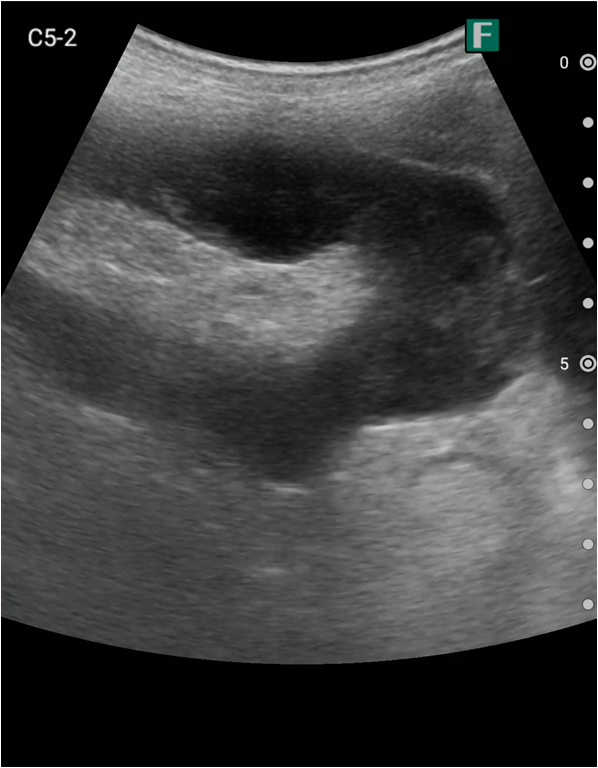

実際に、私がiViz airを使用した具体例を2つ紹介します。1つ目は救急外来での事例です。

夜間、腹痛を主訴に高齢の男性が救急外来にいらっしゃいました。その方は尿道カテーテルが入っており、頻繁にカテーテルの閉塞を起こしている病歴がありました。

視診を行い下腹部に軽度の膨隆が確認できましたが体外から出ているカテーテルには明らかな閉塞を認めませんでした。そこで、iViz airで観察したところ、膀胱内に約400mlの残尿を認めカテーテル閉塞による腎後性腎不全と診断を確定させることができました。尿道カテーテルを抜去した際、外見からは見えないカテーテルの先端部分に沈殿物を認め、閉塞の原因であるとわかりました。その後尿道カテーテルの交換を行うと残尿の排出ともに腹痛は消失し、無事に帰宅されました。iViz airでの観察が尿閉の確定診断につながった症例です。